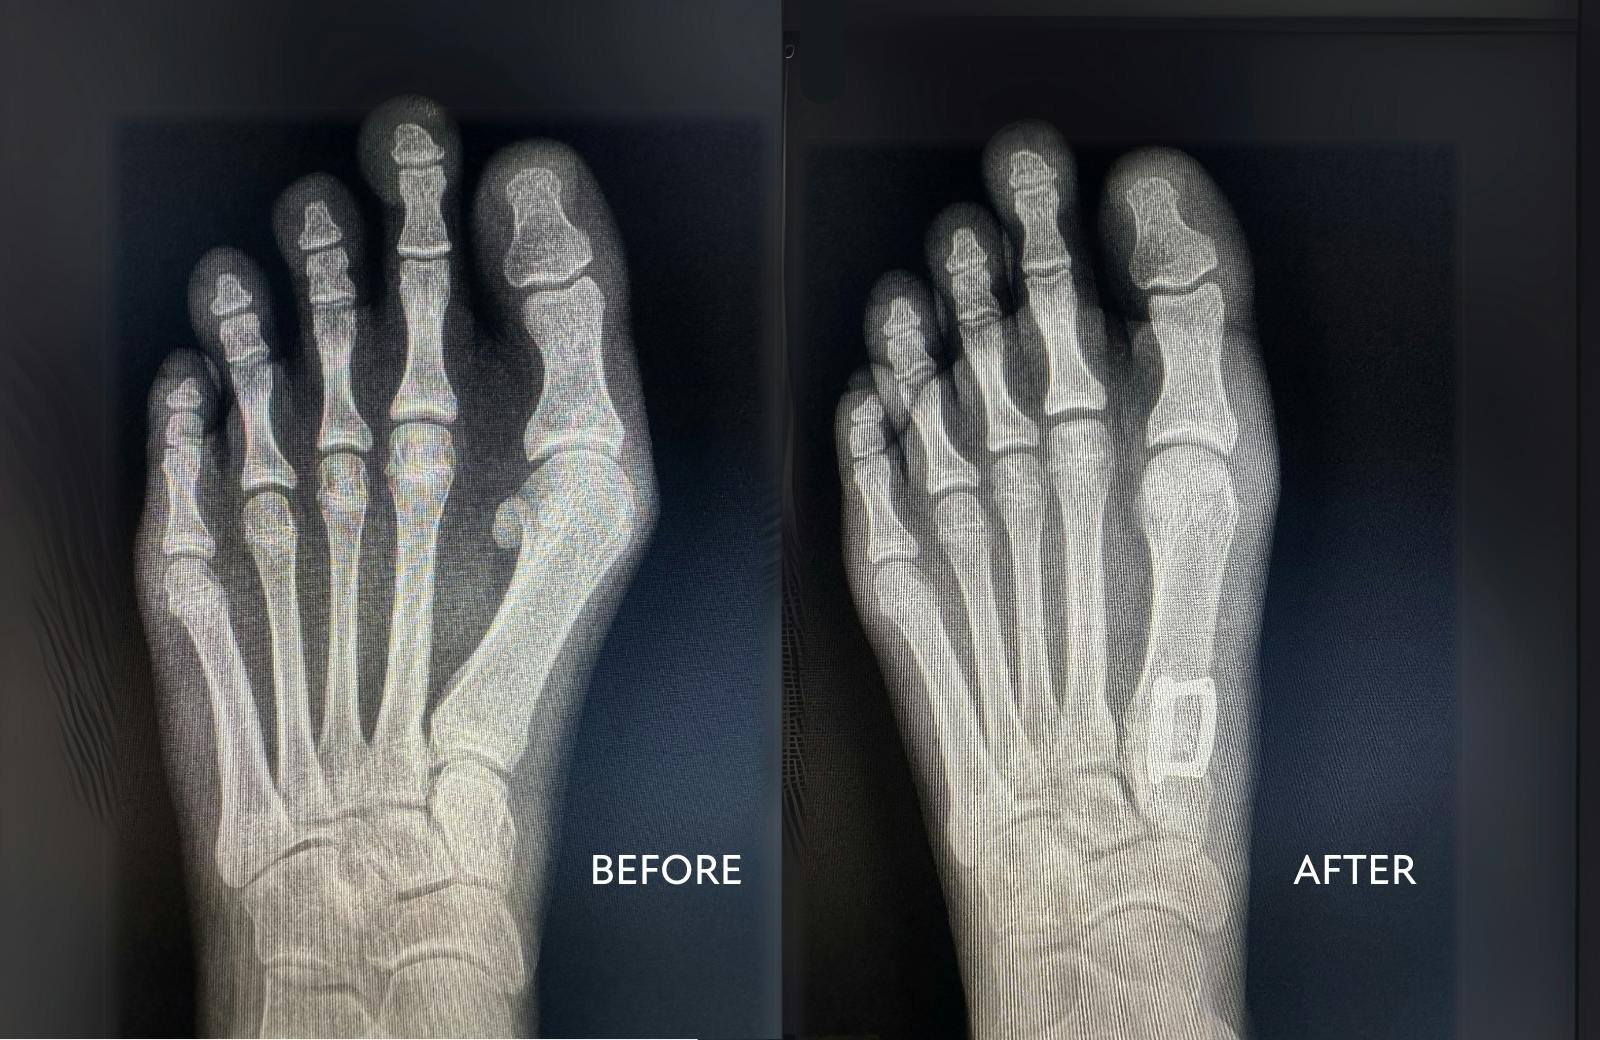

CLS Health offers a variety of bunion surgery options to address your specific needs. Bunionectomy, which corrects misaligned bones in the big toe, can significantly reduce pain and improve mobility. If you're considering bunion surgery, our foot and ankle specialists can help you determine the best approach.

Unlike traditional bunion surgery, Lapiplasty® corrects the deformity in all three dimensions, stabilizing the joint to prevent recurrence. Patients can walk within days instead of weeks.